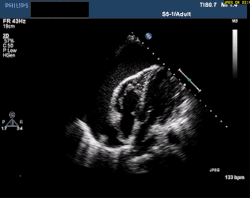

انصباب التامور (بالإنجليزية: pericardial effusion) هو عبارة عن تجمُّع لسوائل زائدة حول القلب.[1][2][3] يحاط القلب بتركيب كيسي ثنائي الطبقة يدعى التّامور، يحتوي الفراغ بين هاتين الطبقتين على كميّة قليلة من السائل.

![]() مخطط صدى القلب ثنائي الأبعاد يظهر الانصباب التاموري عبر الصدر. وتظهر القلب المتمايل. مخطط صدى القلب ثنائي الأبعاد يظهر الانصباب التاموري عبر الصدر. وتظهر القلب المتمايل. | |

يحدث الانصباب التّاموري عادةً بسبب التهاب التأمور نتيجة مرض أو أذيّة ولكن يمكن أن يحدث بدون التهاب. كما يمكن أن ينتج انصباب التأمور عن تجمع للدّم تالي لإجراء جراحي أو أذية.

عندما يتجاوز حجم السائل مستوى كفاية التامور، يؤدّي الانصباب التّاموري إلى ضغط على القلب مسبباً ضعفاً في الوظيفة القلبيّة. إذا لم يعالج انصباب التأمور يمكن أن يؤدي إلى قصور القلب أو الوفاة.